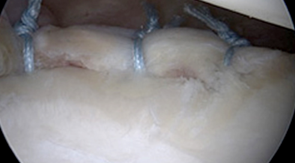

어깨 탈구에 의한 전방 관절와순 파열

수술 전

어깨 탈구에 의한 전방 관절와순 봉합술 후